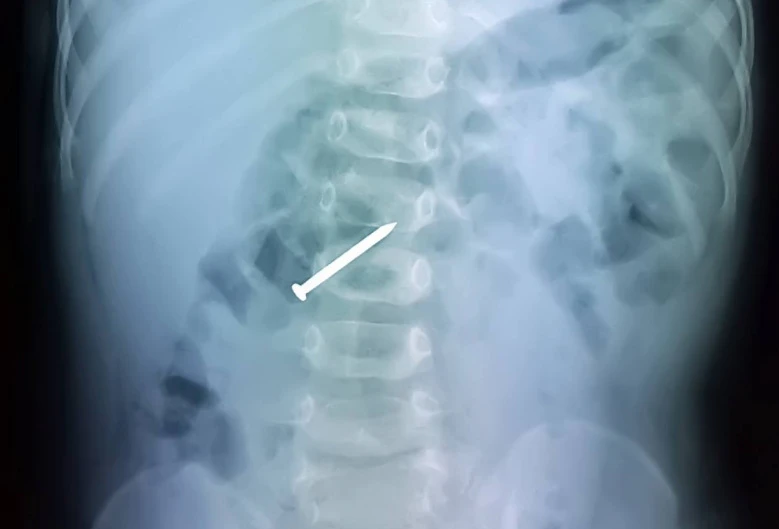

Tại đây, bé P. được khám lâm sàng và chụp X-quang. Kết quả cho thấy một cây đinh nằm ở khung tá tràng. Sau khi hội chẩn nhanh giữa các chuyên khoa, bé P. được chuyển ngay đến phòng mổ.

Kết quả chụp X-quang cho thấy cây đinh nằm ở khung tá tràng của bé P. Ảnh: LÊ PHỤNG